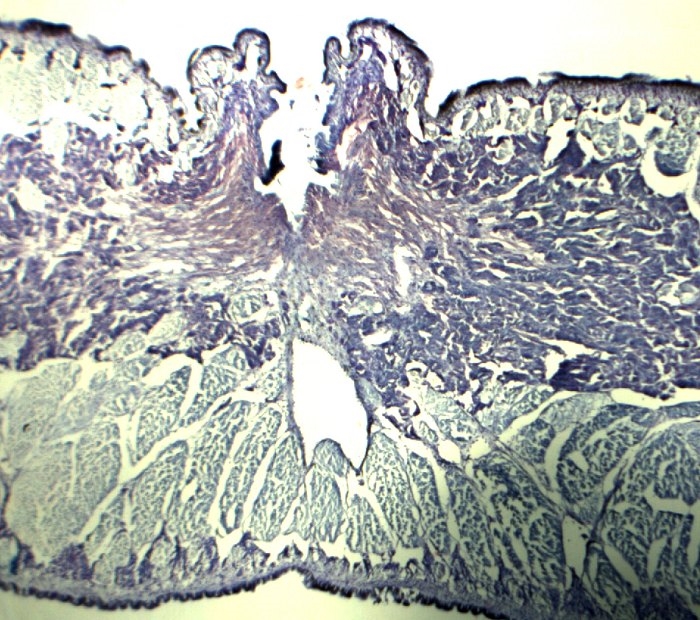

Hier zu vergleich ein Schilddrüsse von Novex B mit ein CP 4500. Damals war ich hiermit aber zufrieden.

Das zweite Bild ist ein Teil von die Wirbelsäule von eine Maus mit rechtsoben das Rückenmark. So ist es jetzt und ist einfach besser.